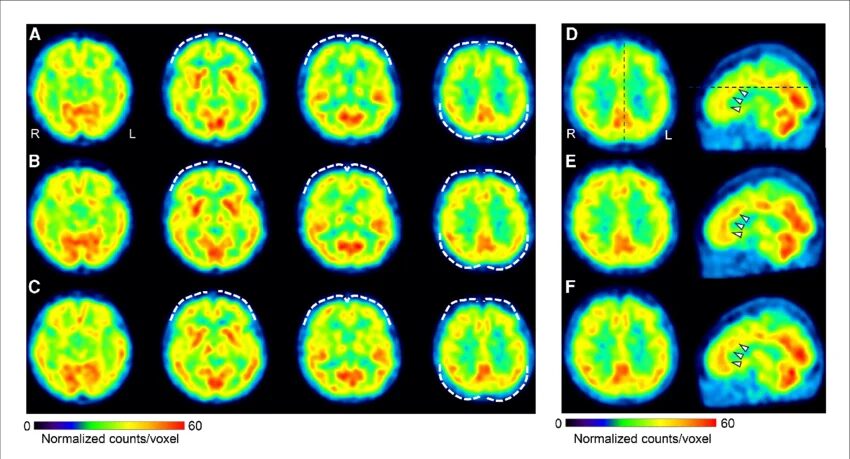

③ PET(陽電子放出断層撮影)1970年代

原理

放射性トレーサーを使い脳代謝を測定。

測定内容

- グルコース代謝

- 神経伝達物質

- 血流

意義

精神疾患研究に革命。

例:うつ病→ 前頭葉代謝低下